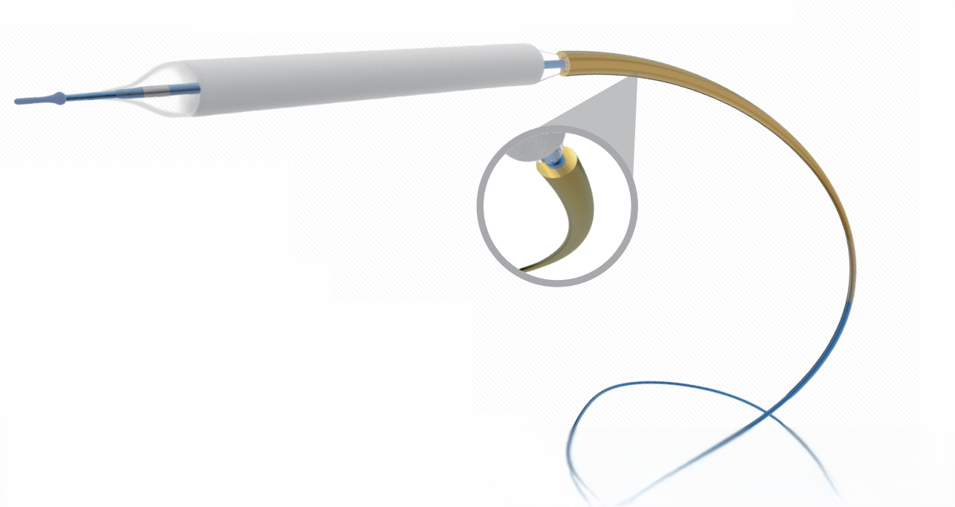

1)保护套设计:采用了类似自膨式支架的保护套设计,该设计有两大优势,首先是DCB到达靶病变位置后,再释放扩张,实现了100%零掉粉;其次是没有赋形剂选择和药物结晶形式的限制,在设计的时候可以不用太顾虑输送过程中掉粉的问题,以提高药物的释放和转载速度优先;

鞘管保护套设计有利于降低球囊在穿过鞘管过程中以及推送过程中的药物损失,最大限度减少远端血管栓塞风险和提高药物的利用率;